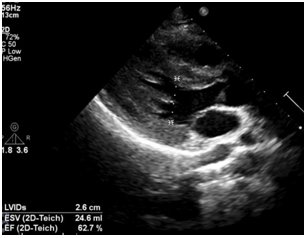

A 21-year-old healthy woman presented to emergency department complaining of severe gluteus pain and progressive dyspnea about one hour after domestic accidental “black scorpion” sting. Despite early scorpion antivenom administration, advanced airway and intensive critical care were promptly required, due to refractory acute respiratory failure (ARF), endorsed by a critical PaO2/FiO2 of 48. Chest computed tomography revealed diffuse bilateral infiltrates and air bronchograms compatible with acute respiratory distress syndrome. Cardiac troponin levels continuously rose. Initial transthoracic echocardiogram (TTE) revealed diffuse hypokinesia causing moderate left ventricle (LV) systolic dysfunction – rest LV ejection fraction (LVEF) of 0.39 (Simpson´s method) (Figure 1). Inotrope at low doses (dobutamine 5mcg/kg/min) was then initiated. Follow-up (ninth day) TTE (Figure 2) and cardiac magnetic resonance (CMR) imaging endorsed reversal of initial contractile dysfunction. At eleventh day patient was uneventfully discharged home.

Figure 2 Control transthoracic echocardiogram showing left ventricular ejection fraction of 0.63 (Teichholz´s method) due to recovered myocardial contractility.